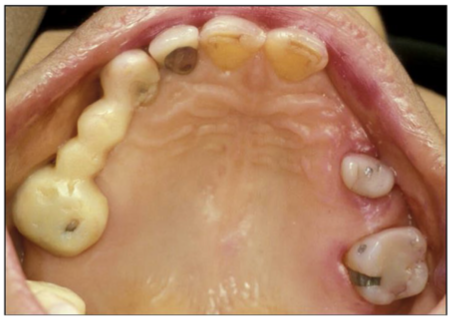

This patient arrives in your office on a Monday morning. He states that he wants a permanent bridge placed on his upper right to replace to replace the failing temporary bridge. Which of the following is NOT required in order to decide if this is an appropriate treatment for this patient?

a) diagnostic casts

b) identifying esthetic desires

c) analysis of the patient occlusion

d) full mouth radiographs

e) all of the answers are required

A